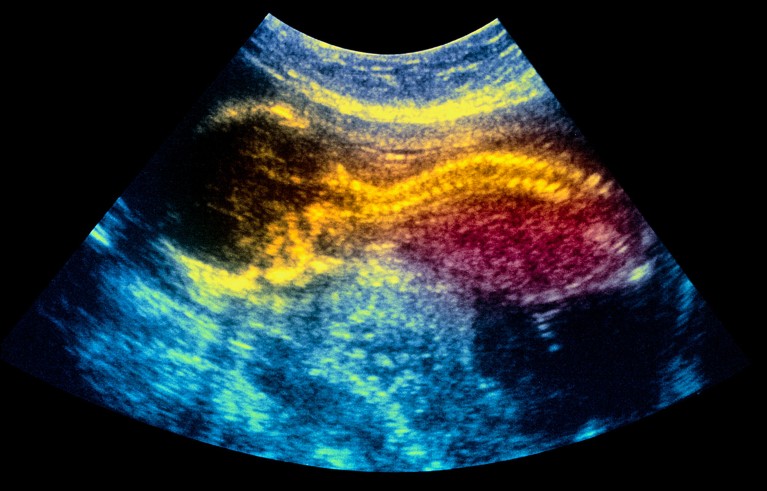

An in utero treatment using placenta-derived stem cells could treat infants with a neural-tube condition called spina bifida. Credit: Simon Fraser/Science Photo Library